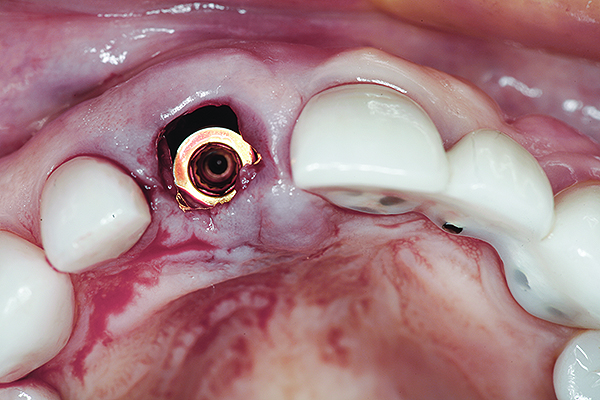

An osteotomy that used the dense cortical bone on the palatal aspect of the extraction socket was prepared, and a guide pin was inserted (Figure 5) to verify that the angulation was ideal. The implant was then inserted (Figure 6). Figure 7 shows the occlusal view of the implant in position. Note the gap between the palatally oriented implant and the buccal plate of the extraction socket.

Fig 7. Occlusal view of the implant after insertion.

Figure 7